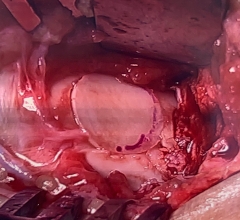

Donor allograft talus with OATs plug removed

The OATS procedure consists of grafting a section of articular cartilage from a non-weight bearing area to the defect of concern. The cartilage graft is removed with the underlying bone. The recipient site is prepared by drilling a socket that will accommodate the graft. The graft is then inserted into the prepared site.

An allograft transplant utilizes an articular cartilage and bone graft similar to the OATS procedure, but the graft is harvested from a cadaver donor.